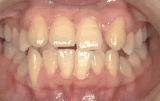

症例1/前歯が出ているのが気になる

【歯科治療前】